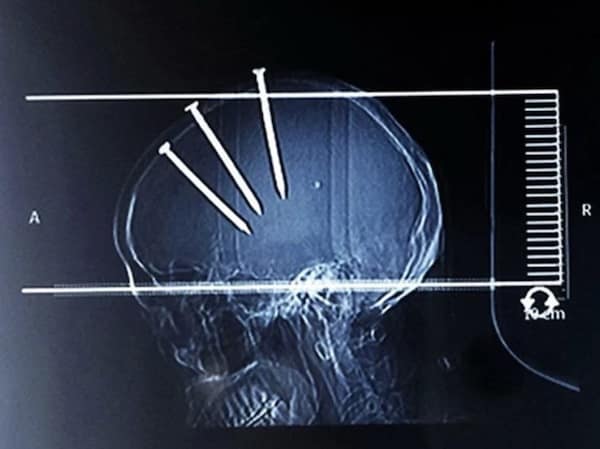

Weird xray photos

I used to think that nothing could surprise me anymore—until I stumbled upon some weird x-ray photos that made me reconsider my stance on human ingenuity (or lack thereof). Apparently, some people have a knack for getting objects lodged where they absolutely shouldn’t be. If you’ve ever wondered how not to use everyday items, these images might provide some unintended guidance.

This collection showcases 31 bizarre x-ray images that defy logic and anatomy textbooks alike. Each photo reveals unexpected objects making cameo appearances inside the human body, turning medical imaging into a gallery of the absurd. From common household items inexplicably found in unusual places to anomalies that would leave even seasoned doctors scratching their heads, these images offer a perplexing glimpse into the more “creative” side of medical emergencies. They highlight the intersection of curiosity, misadventure, and perhaps a dash of poor decision-making, all captured through the lens of radiology.